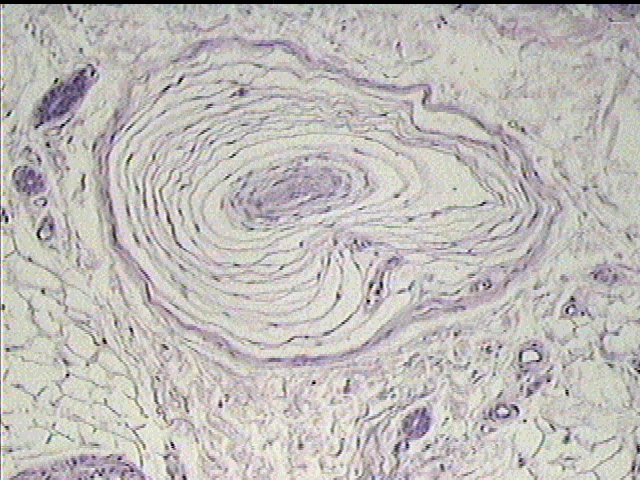

- 7. The Sense Organs : On Microscopic Examination, The Lamellar Structure Of The Corpuscle Is Evident, The Lamellae Giving An Appearance Which Has Been Likened To A Section.

- Cns Physiology - Studyblue - On Microscopic Examination, The Lamellar Structure Of The Corpuscle Is Evident, The Lamellae Giving An Appearance Which Has Been Likened To A Section.

Pacinian corpuscle pacinian corpuscle pacinian corpuscle, with its system of capsules and central cavity.a.